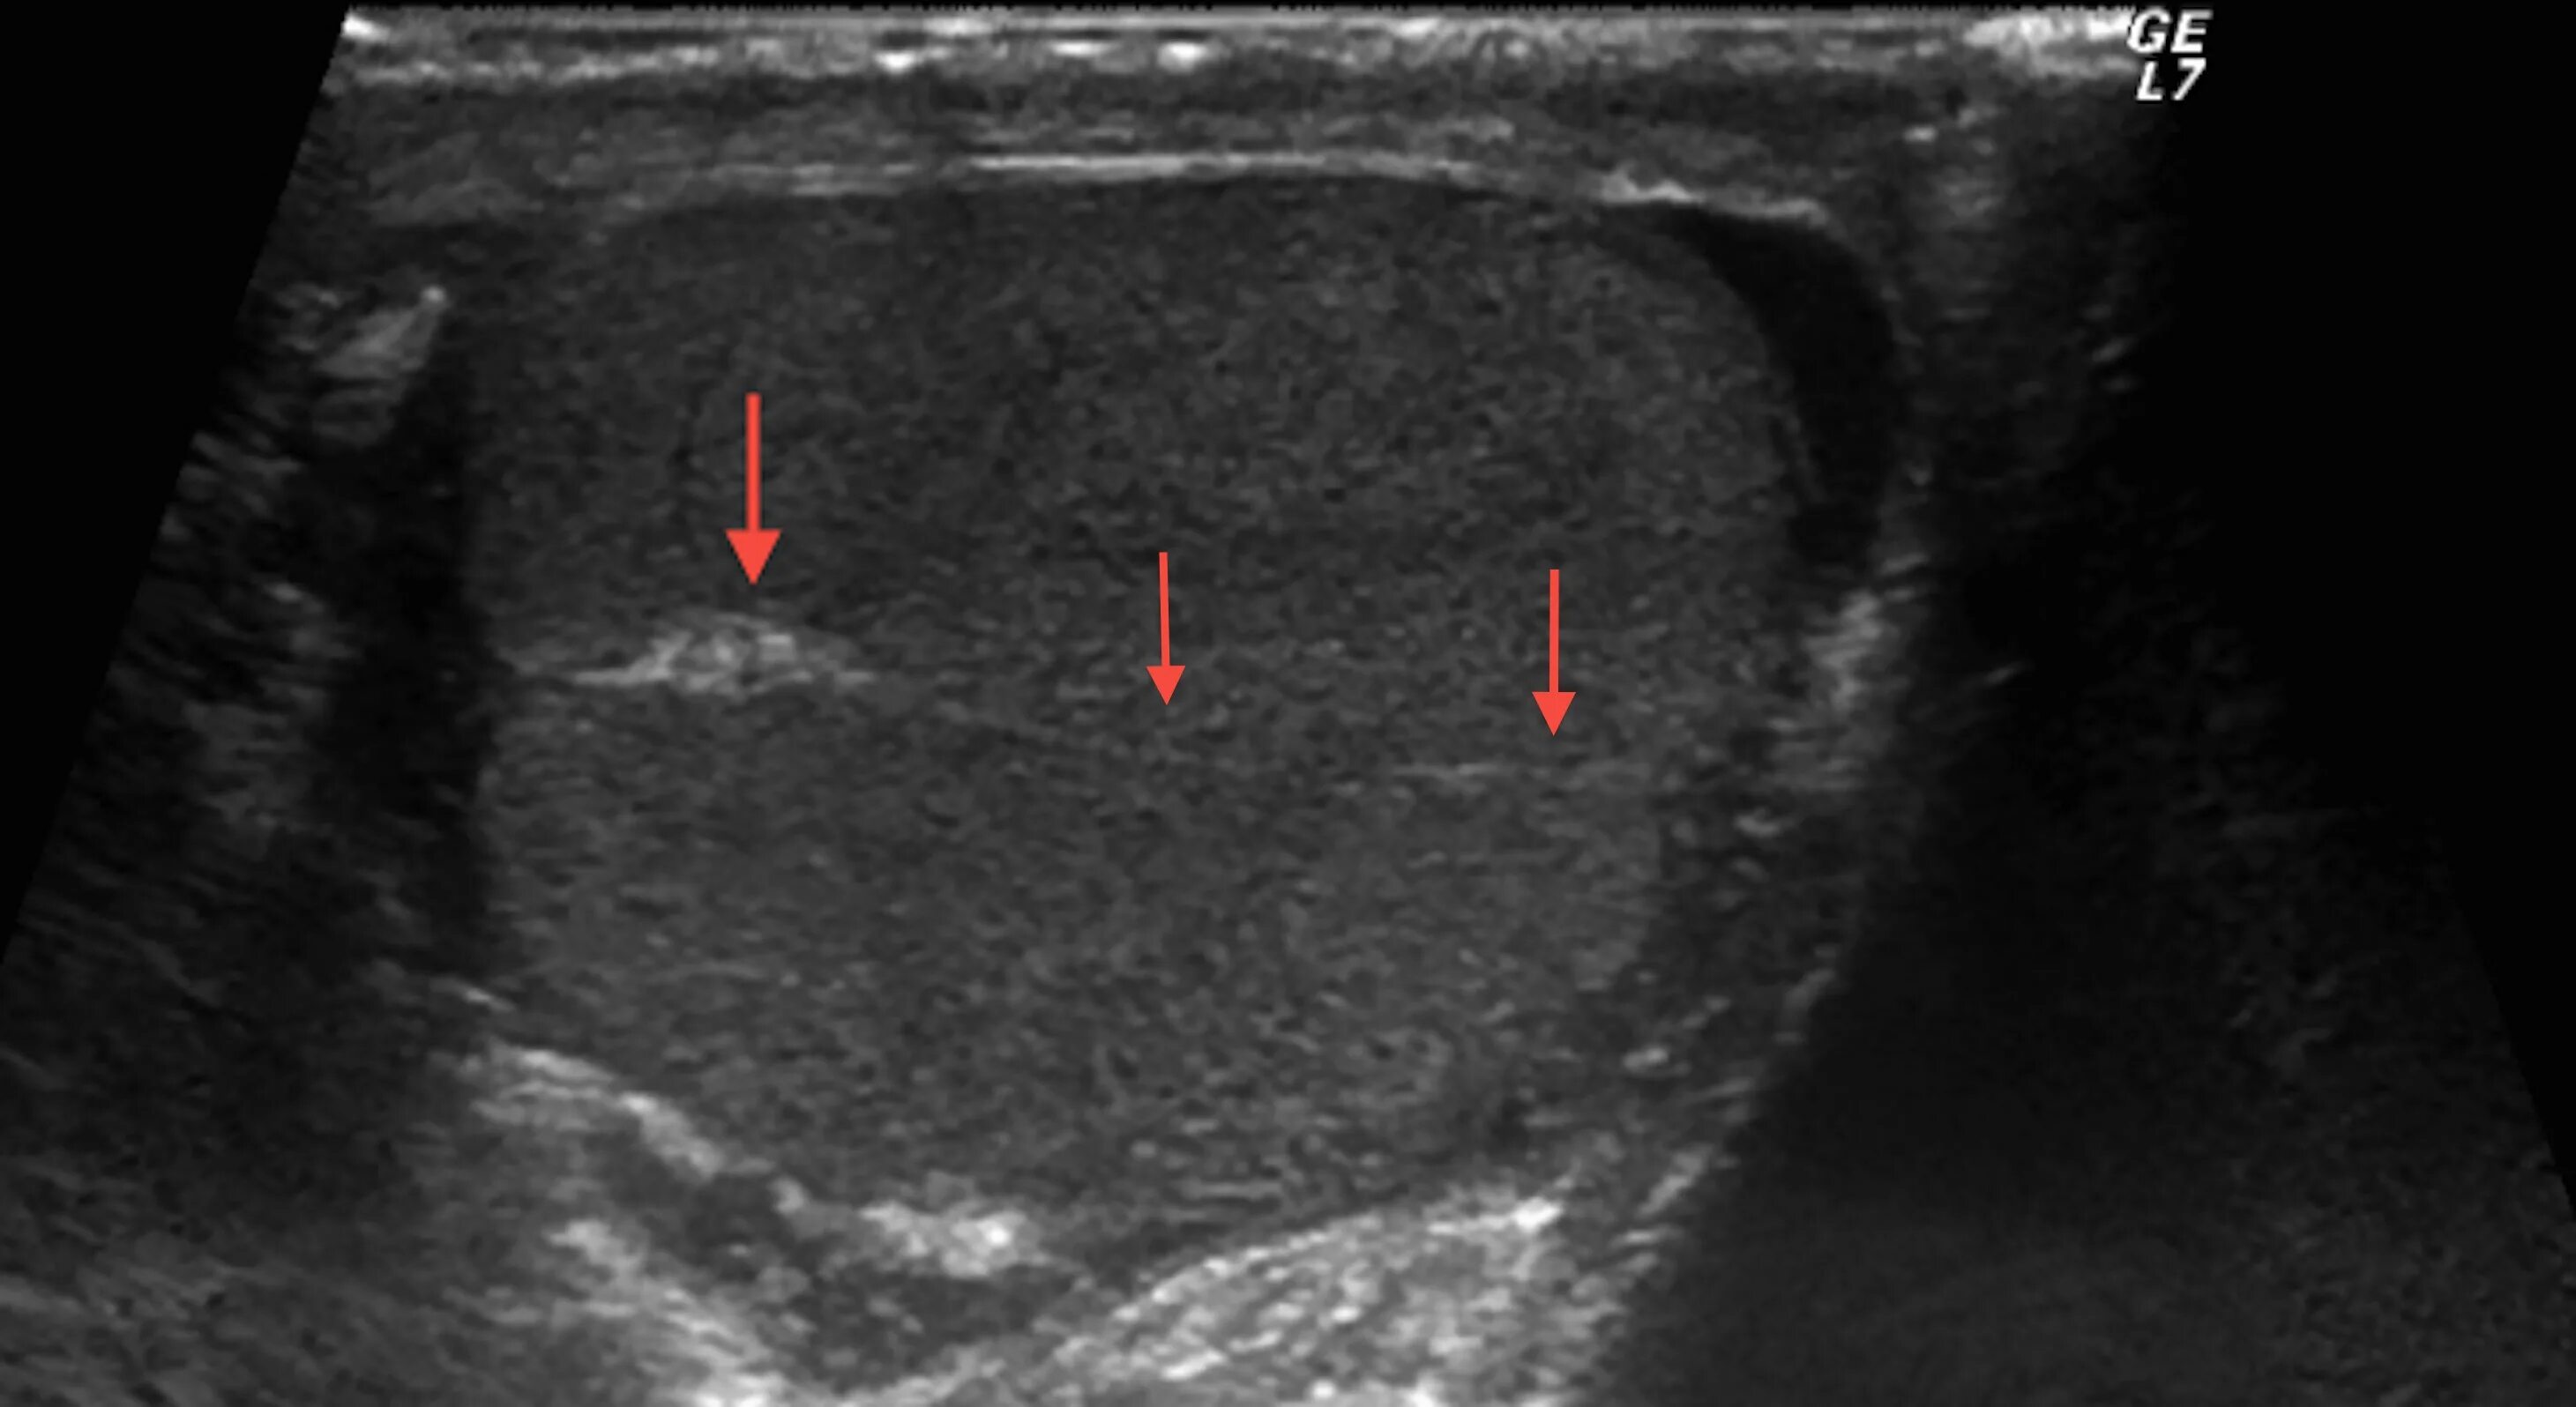

Диффузные изменения яичек